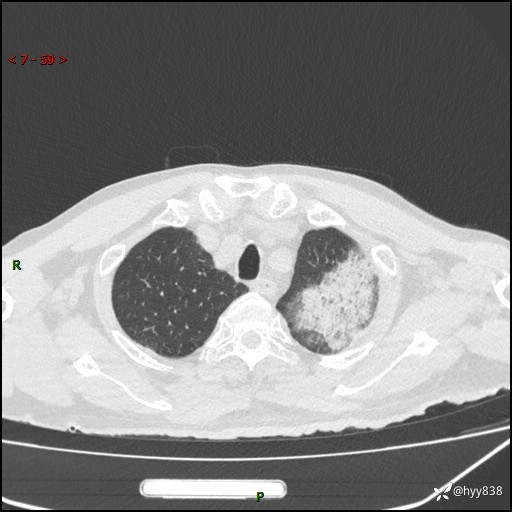

胸部CT平扫(2024.7.24)